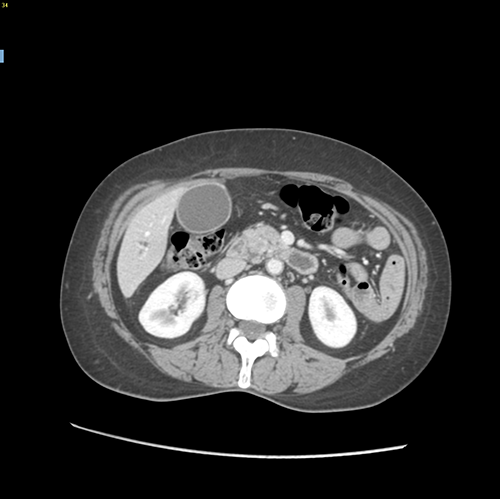

胰头癌-胰十二指肠切除